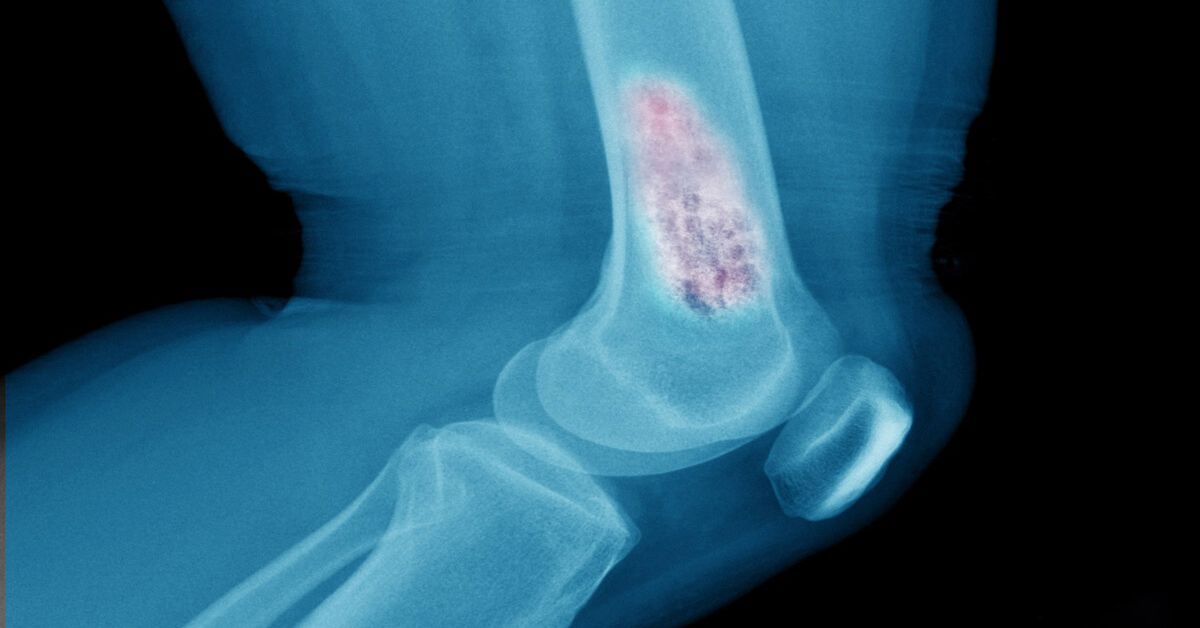

Vücudumuzdaki kas, yağ, sinir, bağ dokusu, tendon veya damar gibi yumuşak dokularda oluşan anormal hücre çoğalmalarıdır. Yumuşak doku tümörü nedir? sorusunun en temel yanıtı; vücudun farklı bölgelerinde iyi huylu veya kötü huylu kitleleri ifade etmesidir. Bu tümörler vücudun hemen her bölgesinde ortaya çıkabilir. Çoğu zaman iyi huyludur ve yavaş büyür. Ancak bazı durumlarda kötü huylu (malign) tümörler de gelişebilir ve bu tür tümörlerin erken fark edilmesi büyük önem taşır.

Yumuşak doku tümörleri, kas, yağ, sinir, damar ve bağ dokusu gibi vücudun yumuşak yapılarında oluşan kitlelerdir. Bu tümörler iyi huylu olabileceği gibi bazı durumlarda kötü huylu da olabilir. Vücudun hemen her bölgesinde gelişebilirler ve çoğu zaman uzun süre belirti vermeden büyürler.

Kesin tanı için görüntüleme ve biyopsi gerekebilir. Çünkü yumuşak doku tümörü iyi huylu mu yoksa kötü huylu mu, ancak bu yöntemlerle anlaşılır. Erken tanı, tedavi sürecinin başarısını artırır. Tedavi genellikle cerrahi olarak yapılır. Bazı kötü huylu tümörlerde radyoterapi veya kemoterapi de uygulanabilir. Her hastanın tedavi planı farklıdır. Bu nedenle uzman bir doktor tarafından kişiye özel bir yol haritası oluşturulmalıdır.